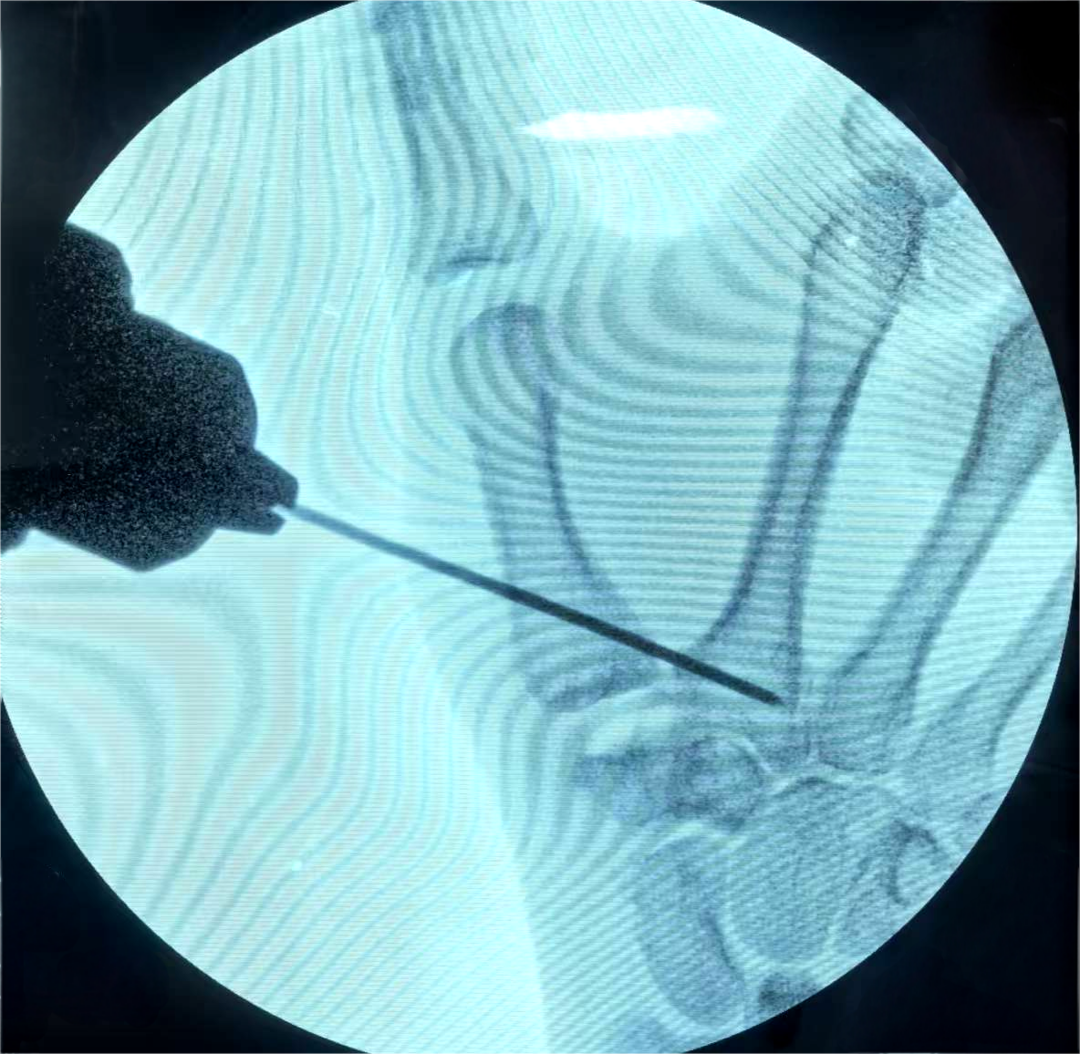

为给患者制定最优治疗方案,张诚主任带领科室医务人员对患者病情进行了全面深入评估,充分结合科室在腕关节镜微创领域的长期技术积淀,最终为患者量身定制了“关节镜下第一腕掌关节成形+第一掌骨克氏针固定悬吊+关节囊皱缩”的微创治疗方案。

手术由手外科、足踝外科主任医师张诚主刀,副主任医师盖茂杨协助完成。术中仅通过关节两侧各约3毫米的微小切口,借助关节镜精准探查并完成全部操作,整个手术历时仅不到一小时就顺利结束。这种微创术式不仅最大限度减轻了手术创伤,更精准保留了拇指关键功能,契合患者对高质量术后恢复的需求。目前,患者恢复良好,已顺利出院,逐步回归正常生活。